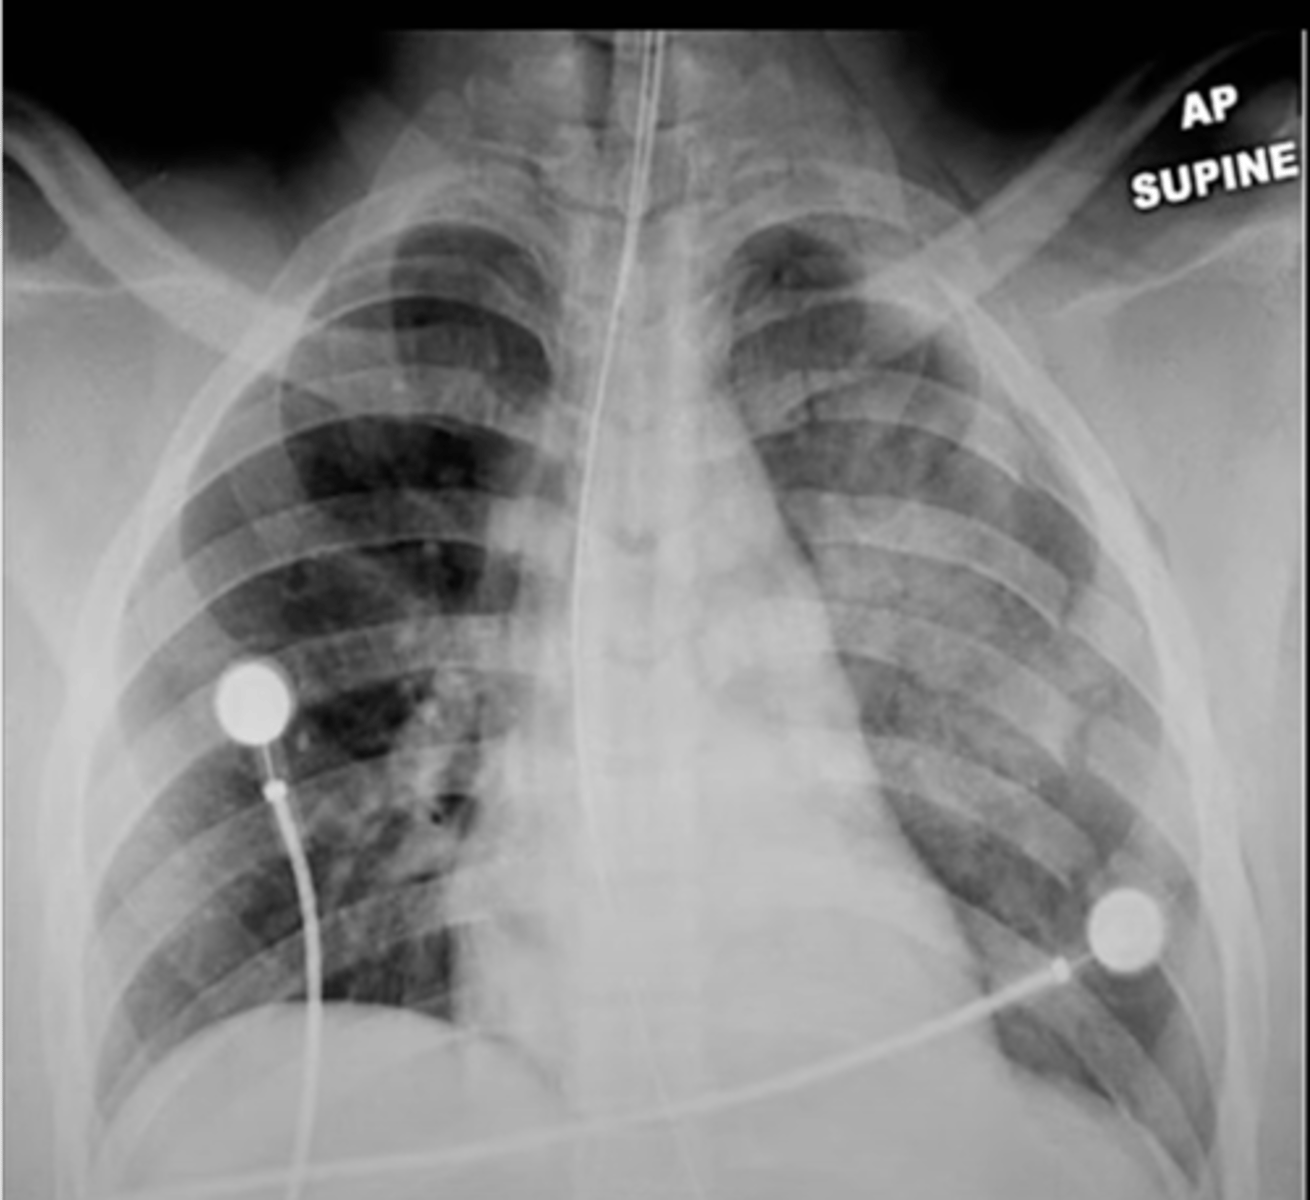

AP View

-pneumothorax on supine radiograph

-costophrenic sulcus will appear lower on one side

Deep sulcus sign meaning

-effusion: tip posteriorly and inferiorly

-pneumothorax: tip anteriorly and superiorly

Chest tube